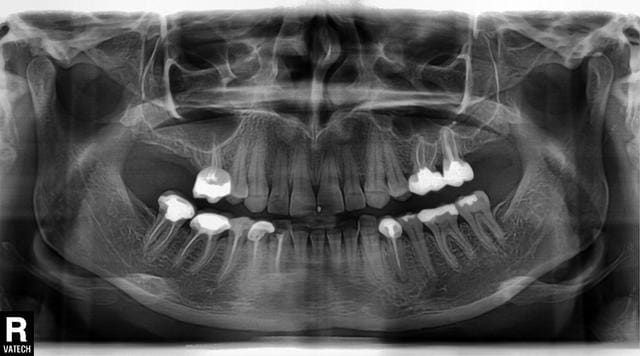

A la panoramique, j'ai noté une carie sista 2-2 en distal de 37 et une parodontite apicale chronique sur 34 (asymptomatique)

-l'apex de la 34 est louche sur la pano... est ce la superposition avec le foramen mentonnier???

Je peux me tromper, mais le trou mentonnier semble ici situé en regard de l'apex des 5, des 2 côtés.

Ensuite, je pense qu'il s'agit du forament mentonnier, au niveau des 5, on a la meme chose au niveau de 45.